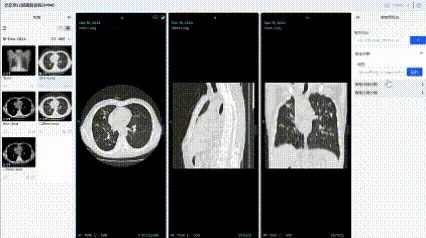

规模大、维度全、安全可信的高质量数据集。中国联通联合国内多家顶尖医疗机构,构建了覆盖影像、诊疗、药品等全维度的高质量数据集,其中,数据集总规模达 100TB,胸部CT影像数据集标注2万余例,肺结核辅助诊断模型准确率超95%;耳部CT影像数据集标注5000余例,听觉障碍识别准确率达95%;肾脏病慢病管理数据集整合1万例患者全周期数据,风险预警模型准确率突破95%;药品说明书数据集涵盖58000份药品信息,实现用药风险智能解析与动态评估。

在数据治理与管理方面,中国联通依托北京市全民言息平台,构建医疗健康行业可信空间,制定数据脱敏规范,运用数据沙箱和隐私计算双引擎处理数据,确保“原始数据不出域、数据可用不可见”。建立11项数据治理全流程运营标准,通过多维度举措保障数据质量与安全。例如,在胸部CT影像数据标注中,采用双盲标注和专家抽样审核,确保标注一致性评估结果超95%,准确性达98%以上。

高效、准确的系列医疗专科智能体。基于该高质量数据集,中国联通研发了一系列医疗专科智能体。基于胸部CT影像的肺结核疾病筛查与诊断模型智能体,准确率超 95%,可实现分钟级快速检测;肾脏病慢病管理干预模型智能体、耳部疾病辅助诊断模型智能体,助力医务人员提高诊断效率及诊疗方案准确性;药品全生命周期智能评估模型智能体,为药品研发、监管等提供全链条数据支撑。